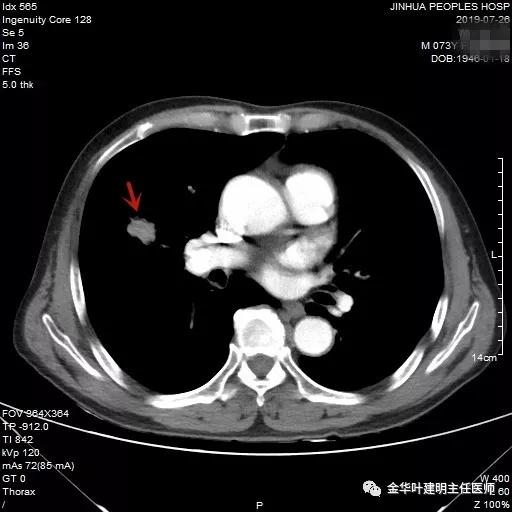

吴某不同意肺穿刺,咳嗽咳痰好转后就出院了。此后于今年6月份回院复查,仍然住在内科,这次想通了,同意肺穿刺,结果病理果然是肺癌,是低分化鳞癌。因为吴某与本院一院级领导是同村的,便让我去会诊。我觉得虽然从病灶来看可以手术,纵隔内也无明显转移的肿大淋巴结,相关检查也无远处转移证据。但患者年纪较大,平时有慢支与肺气肿,发作时还有喘憋症状,肺功能也示重度混合型通气功能障碍,MVV重度下降。询问吴某,平时一口气走上3楼是有困难的,所以行右肺上叶切除术后出现呼吸功能不全的概率还是比较高的,手术存在较大风险。争取手术也是为争取根治以至得到较长期生存的机会。若同意手术,也要家属与患者都十分理解,并对术后需要呼吸机辅助以及无法脱离呼吸机支持都有充分的思想准备。而若放弃手术,则主要是免疫治疗及放化疗,其中放化疗对肺功能也有一定影响,且无法达到根治的目的。我当时告诉吴某儿子,要开,做好术后出现呼吸功能衰竭的准备,且不能责怪我的同事和我本人;若暂不手术,也可回当地考虑保守治疗;当然也可先戒烟、锻炼肺功能、使用支气管扩张剂等改善肺功能,较短时间内再回院复查肺功能,再争取手术。吴某当时办理了出院手续,也没有与我们确认是否考虑手术。下面是当时6月份时候的片子以及肺穿刺情况:

绿色箭头示穿刺针,红色箭头示肿瘤